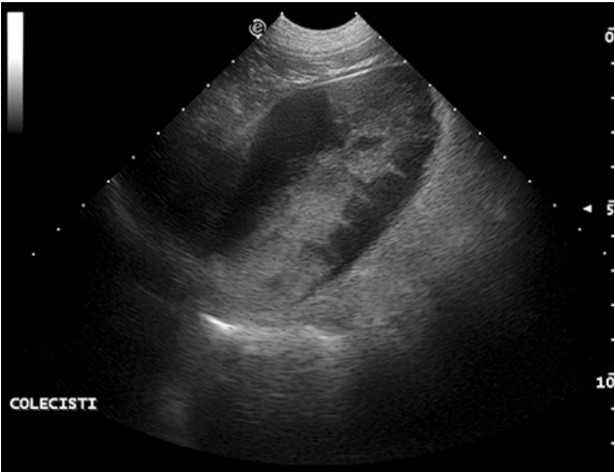

سونوگرافی طحال همیشه باید در طول یک سونوگرافی معمول شکم گنجانده شود و همچنین در برخی شرایط حاد مانند ولولوس معده که طحال ممکن است در پیچ خوردگی درگیر باشد نیز لازم است. (شکل 2).سونوگرافی همچنین در ارزیابی / پیگیری توده های طحال نشان داده می شود. توجه در رویکرد اولتراسونوگرافی توده های گسترده پیچیده که حاکی از پارگی احتمالی است که باعث خونریزی تهدید کننده زندگی می شود، درخواست می شود.

شکل2. پیچ خوردگی طحال در ژرمن شپرد نر 5 ساله. طحال ظاهری V شکل با حاشیه های گرد دارد. پارانشیم طحال بیهوشی است که با لکههای نازک پراکنده پراکنده مشخص میشود.